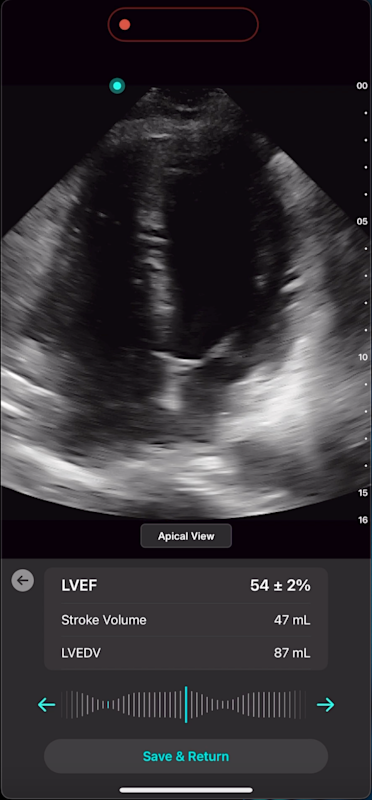

Cardiac AI

With Exo’s Cardiac AI, you can measure left ventricular ejection fraction (LVEF) and stroke volume in a few heartbeats in both parasternal long axis (PLAX) and apical four-chamber (A4C) views, making it easier than ever for POCUS users to get to answers.